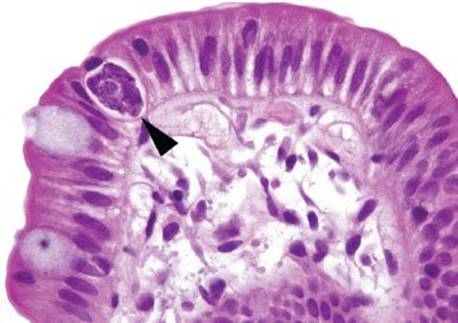

Figure 3.317 Isosporiasis. On higher power, a slight prominence of lamina propria eosinophils serves as a red flag to the diagnosis. Arrowheads highlight the Isospora organisms, which are obligate intracellular parasites and are found in the paranuclear or subnuclear cytoplasm.

Figure 3.318 Isosporiasis. On higher power, the Isospora organisms (arrowheads) are seen embedded within the epithelium. Unless the epithelial compartment is diligently inspected in every biopsy, these organisms would almost certainly be missed.

Isosporiasis is among the more common protozoan causes of severe diarrhea in AIDS patients (Figs. 3.316–3.318).190 The Isospora belli organisms are spread via contaminated water or fecal–oral contamination. They localize to the small bowel surface and are exceedingly easy to miss owing to sometimes unremarkable background mucosa and sparsely distributed organisms (Figs. 3.316–3.321). Diagnostic confirmation is facilitated through identification of the oocysts in stool samples or duodenal aspirates.191 Standard therapy consists of trimethoprim–sulfamethoxazole, which is often long term in severely immunocompromised patients.